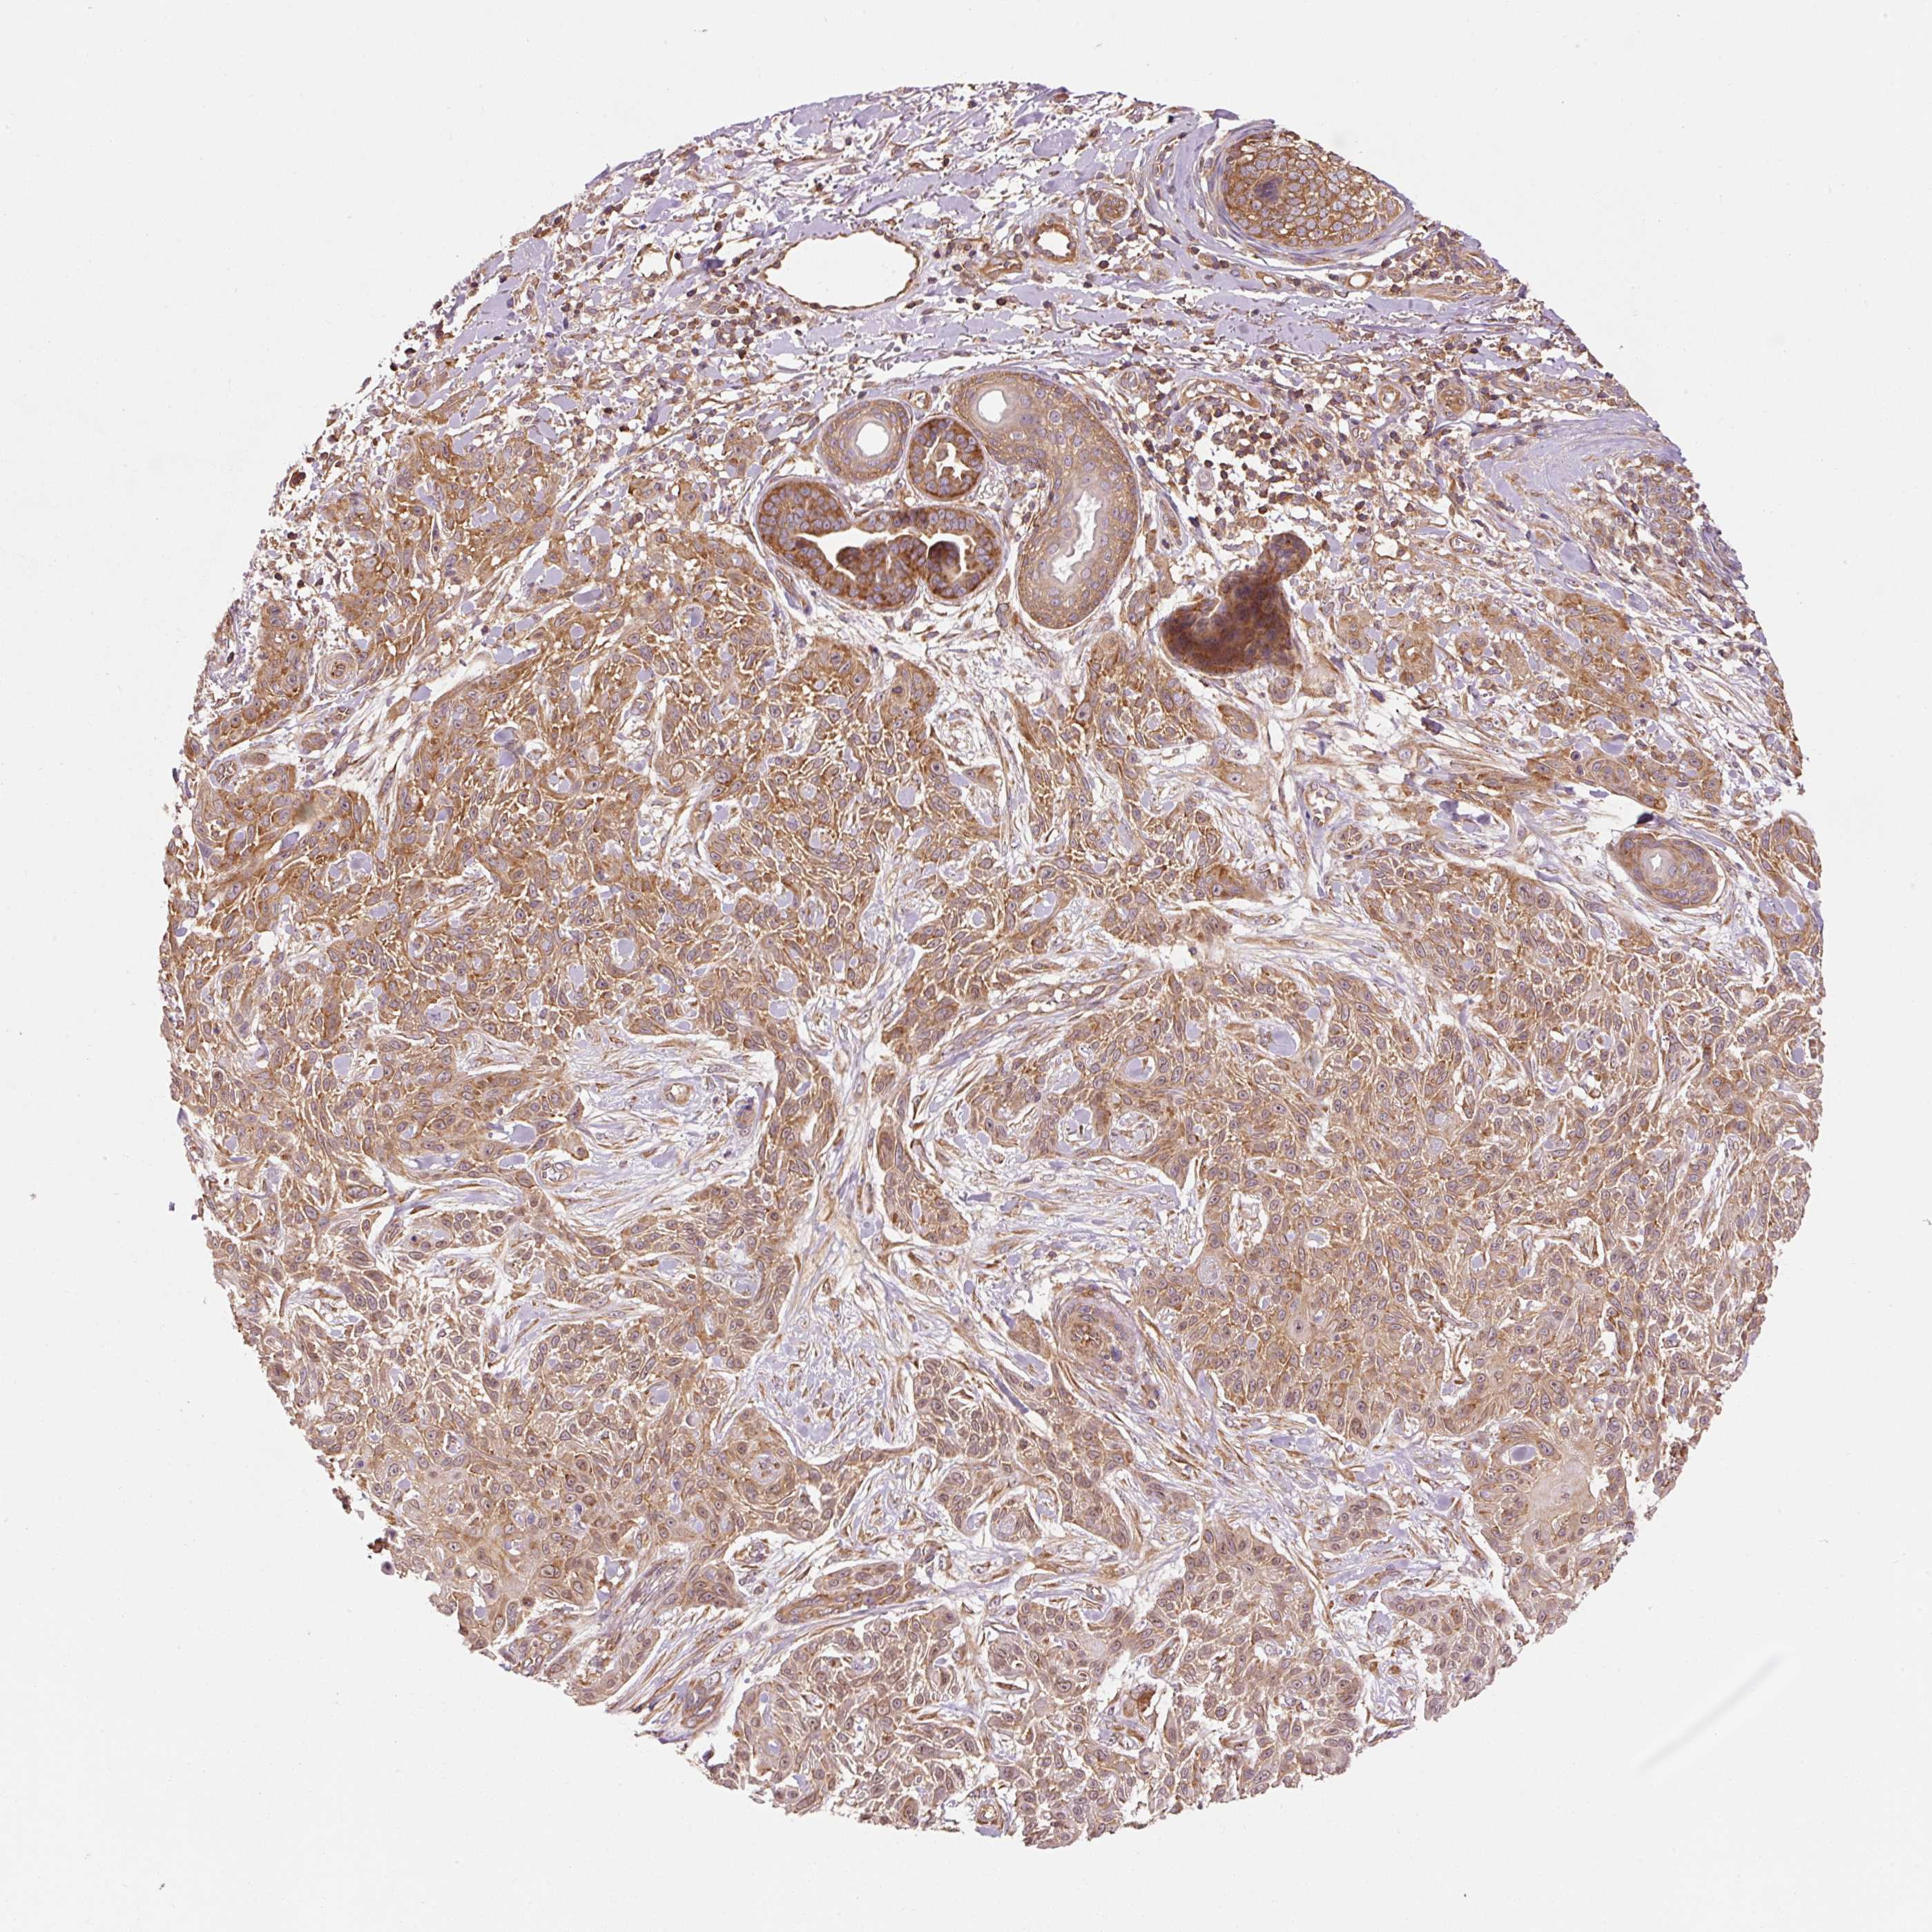

SKIN CANCER - Protein expressioni

A mouse-over function shows sample information and annotation data. Click on an image to view it in a full screen mode. Samples can be filtered based on level of antibody staining by selecting one or several of the following categories: high, medium, low and not detected. The assay and annotation is described here.

Each image is clickable and will lead to virtual microscopy that enables deeper exploration of all samples and also displays staining intensity scores, fraction scores and subcellular localization as well as patient and tissue information for each sample.

Antibody HPA050294

Antibody HPA060836

Antibody CAB021103

Staining

High

Medium

Low

Not detected

Intensity

Strong

Moderate

Weak

Negative

Quantity

>75%

75%-25%

<25%

None

Location

Nuclear

Cytoplasmic/membranous

Cytoplasmic/membranous,nuclear

Basal cell carcinoma

Squamous cell carcinoma, NOS